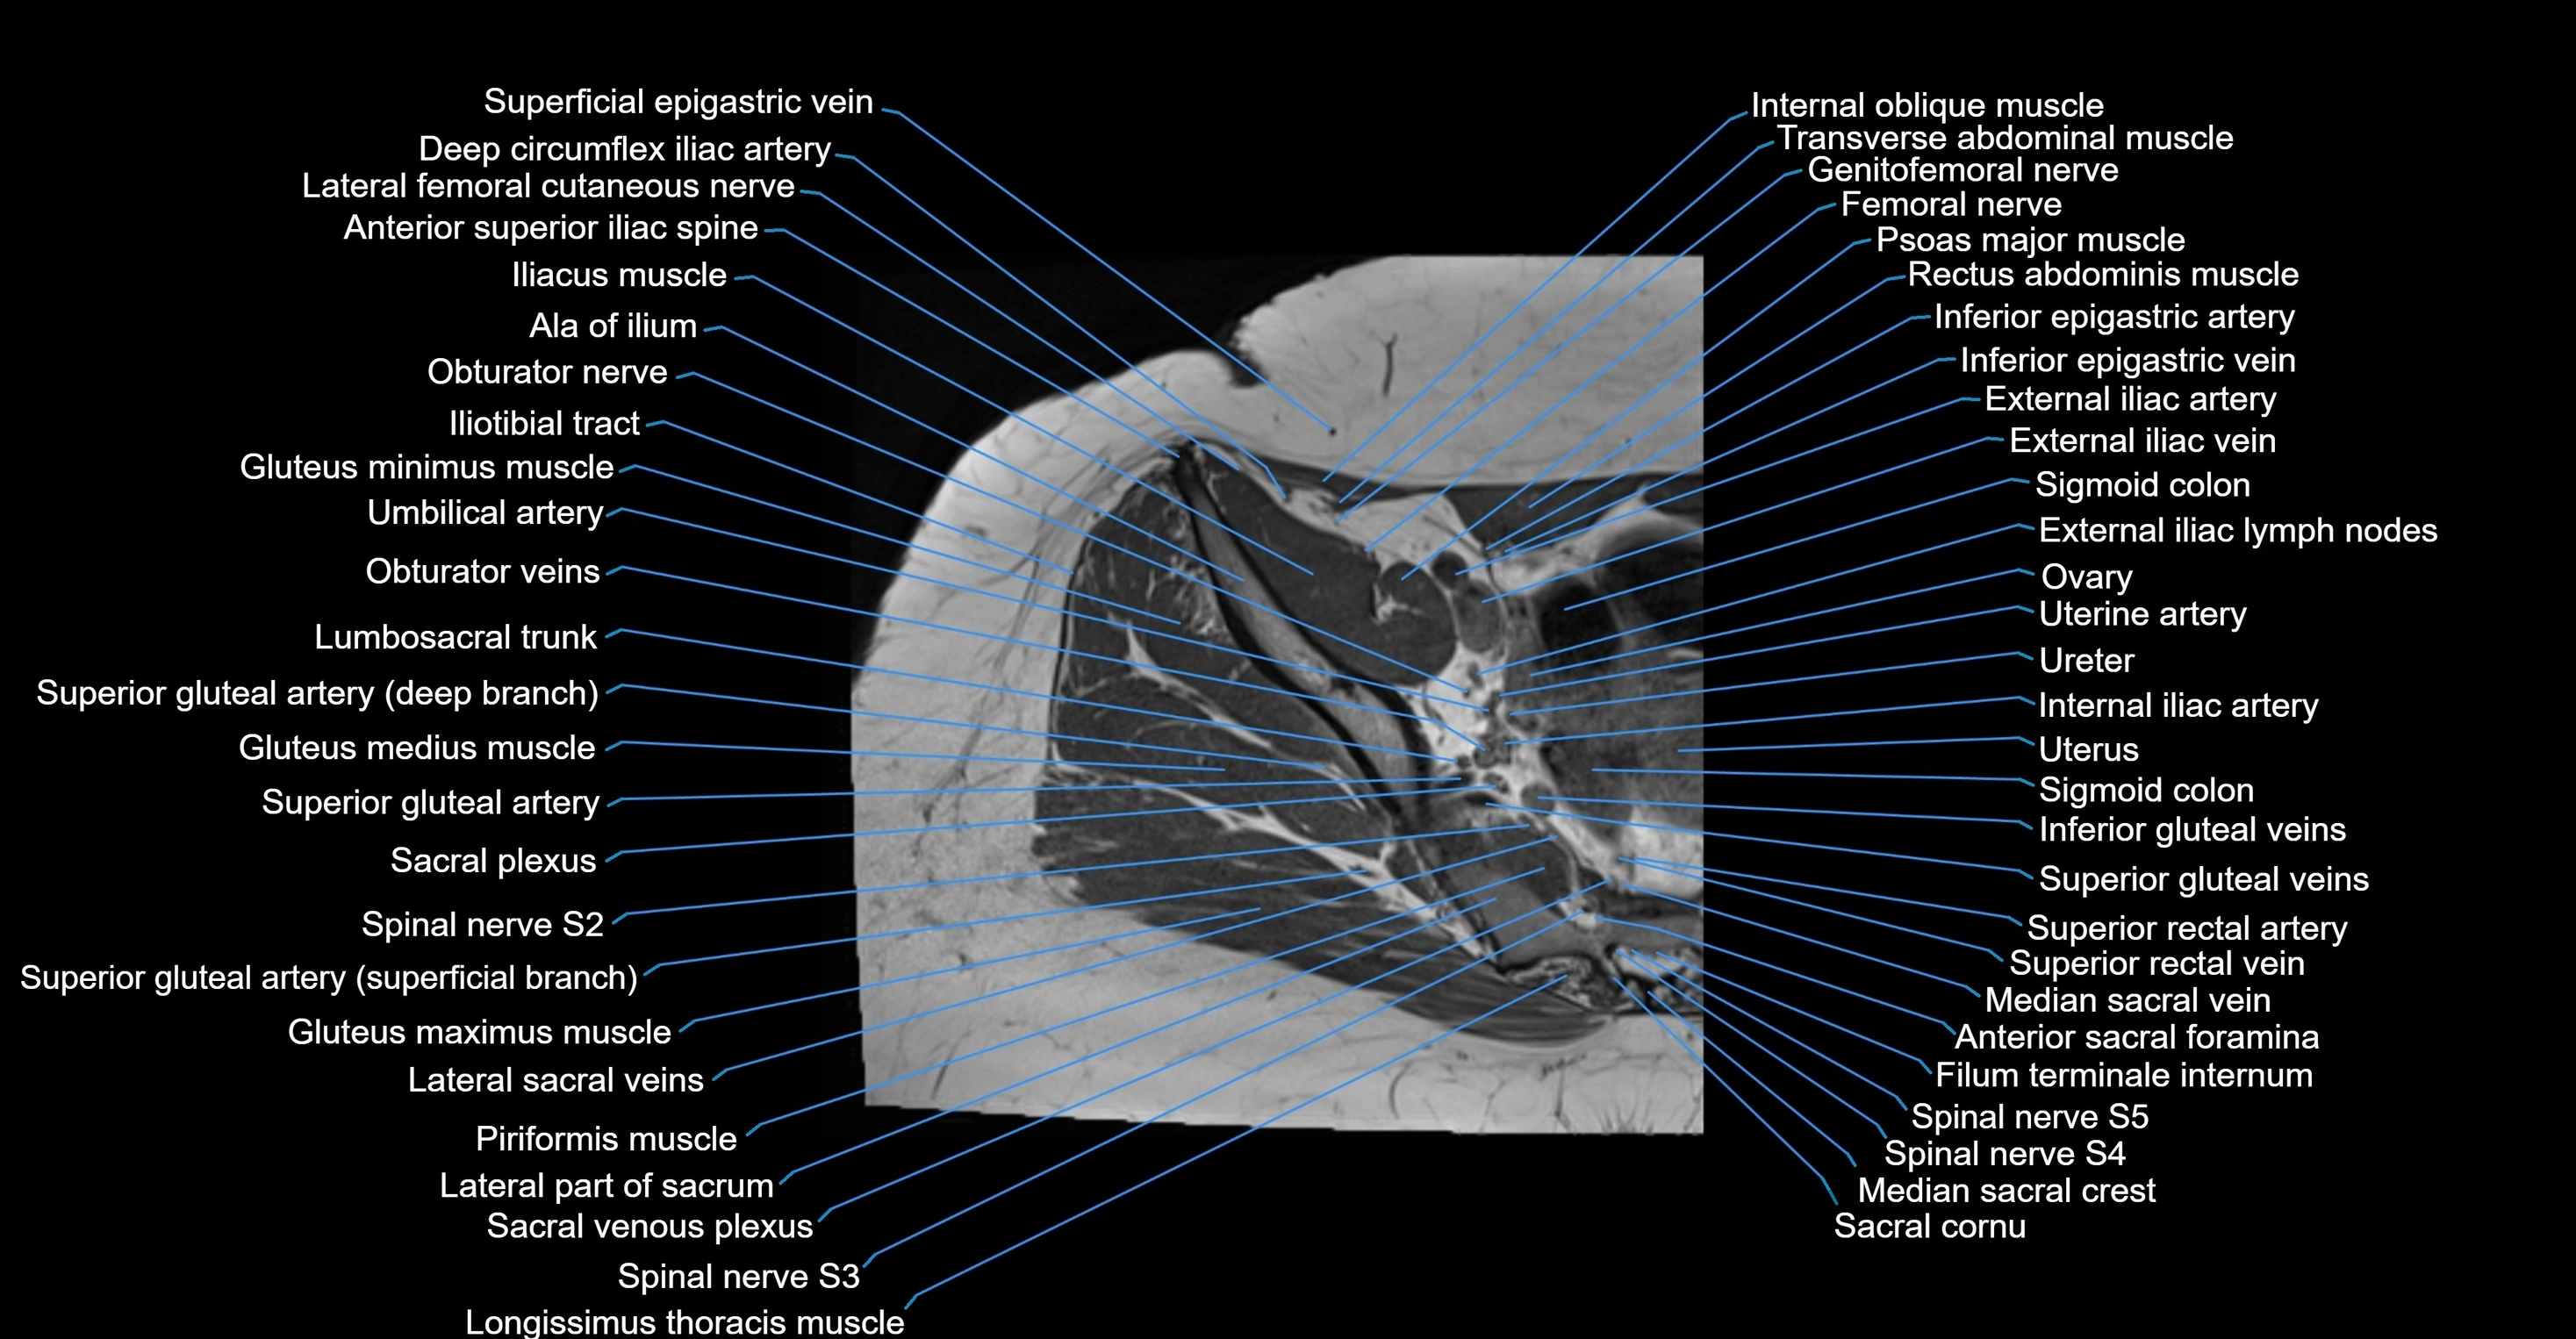

- Anterior sacral foramina

- Deep circumflex iliac artery

- External iliac lymph nodes

- External iliac vein

- Femoral nerve

- Filum terminale internum

- Genitofemoral nerve

- Gluteus maximus muscle

- Gluteus medius muscle

- Gluteus minimus muscle

- Iliotibial tract

- Inferior epigastric artery

- Inferior epigastric veins

- Internal iliac artery

- Lateral part of sacrum

- Lateral sacral crest

- Lumbosacral trunk

- Median sacral crest

- Median sacral vein

- Ovaries

- Psoas major muscle

- Sacral canal

- Sacral cornu (sacral horn)

- Sacral hiatus

- Sacral plexus

- Sigmoid colon

- Spinal nerve S2

- Spinal nerve S3

- Spinal nerve S4

- Spinal nerve S5

- Superior gluteal artery

- Superior rectal vein

- Umbilical artery

- Uterine artery

- Uterus